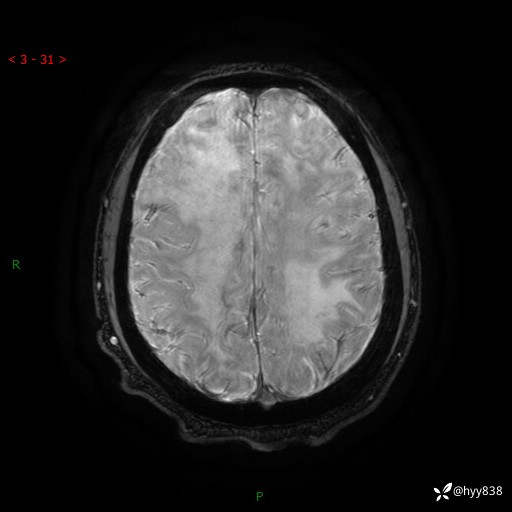

磁敏感成像